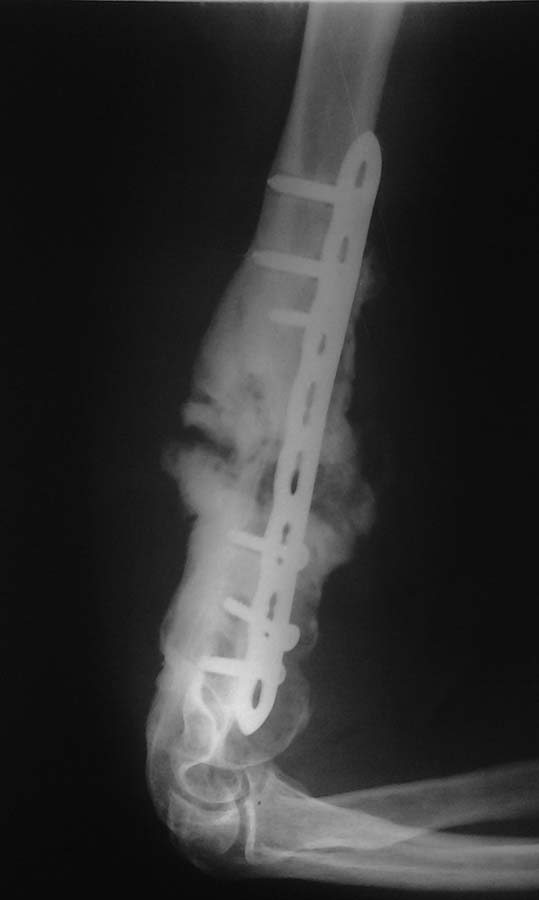

пациент (мужчина 32 лет) пришел удалять пластину, и сообщил что травма 1 год назад, выполнен синтез, через 2 мес. появились боли, которые стихли 1,5 мес. назад. повторные травмы отрицает. объм движений в локтевом суставе удовлетворительный: сгибание до угла 40, разгибание 170-175, явлений неврита нет, имеется патологическая подвижность в н/3 плеча. Уважаемые коллеги выскажите свое мнение по поводу данного случая и что бы вы предложили пациету. Большое спасибо.

Есть мнение,что винты в дистале никто и не блокировал - введены кортикальные компрессирующие - из-за чего и не срослось. Показан реостеосинтез.

Спасибо за замечание. В данном конкретном случае несращение является скорее всего следствием нестабильности конструкции. Если бы в дистале были применены блокированные винты,то возможно нестабильности удалось бы избежать. Применение традиционных кортикальных винтов на LCP пластине возможно, но как правило в комбинации с блокирующими винтами в оба отломка. В этой же ситуации, как мне кажется, введение только лишь неблокированных винтов в дистал нивелировало преимущества LCP.

Снимка непосредственно после операции нет? Избыточная мозоль следствие или некорректного синтеза (диастаз, в свои сроки нет сращения, пластина "как распорка" не дает срастись, в финале ломается конструкция) или избыточная активность пациента до сращения перелома ( "не давал перелому срастись"). Чем короче линия перелома, тем больше показаний для интрамедуллярного синтеза, выбрав такой синтез и хирургу и пациенту надо бы поаккуратнее. Конечно, никакой костной пластики здесь не нужно, с мозолью проблем нет, ее даже с избытком. Пластину удалить. При "полной подвижности" пластину сблизив отломки с помощью контрактора, при тугой подвижности-фиксацию короткой повязкой софткаст или короткой лонгетой с возможностью движений в локтевом суставе и ждать....Срастется!

Несмотря на критику, продолжается показ рентген снимков только в одной проекции. Понимаем, что в интернет сообщениях необходимо краткость и ясность, но трудно без обследования и без необходимых снимков принять важные решения.

Одним из факторов образования ложного сустава является слабая конструкция. Здесь видно обильное мозолеобразование, что означает - сохранилась хорошая биология вокруг пластины. Не все слабые конструкции приводят к ложному суставу, и иногда консолидацию можно коррегировать более близким послеоперационным мониторингом. Коррекциями можно довести слабые фиксацию до сращения. Без наблюдения больные процесс восстановления берут на себя, и в результате нарушается режим. Ранние без контрольные нагрузки приводят к расшатыванию всей конструкции.

О важности хирургической техники и знании доступов говорили много раз. Одиночный снимок не дает возможность ориентироваться. На снимке вроде пластина находится спереди? А в дистальном отделе плеча безопасной является задняя поверхность. Если пластина находится латерально, еще хуже, там нерв! Необычная установка пластин возможна при открытым переломе, где параллельно с обработкой ран, не теряя времени, можно зафиксировать пластиной.

Навряд ли? Пластина для бедра намного толще, чем плечо, и лучше всего подойдет более изящная, но жесткая пластина 3.5 мм для внесуставных переломов от Synthes.

Здесь пластина до сих пор держит плечо по длине, и не снимая пластину можно пробовать нагрузку по оси. Короткий ортез из “софткаста”, в руку трость, и нагрузка при ходьбе! Контроль через месяц, и если нет консолидации тогда ревизия!